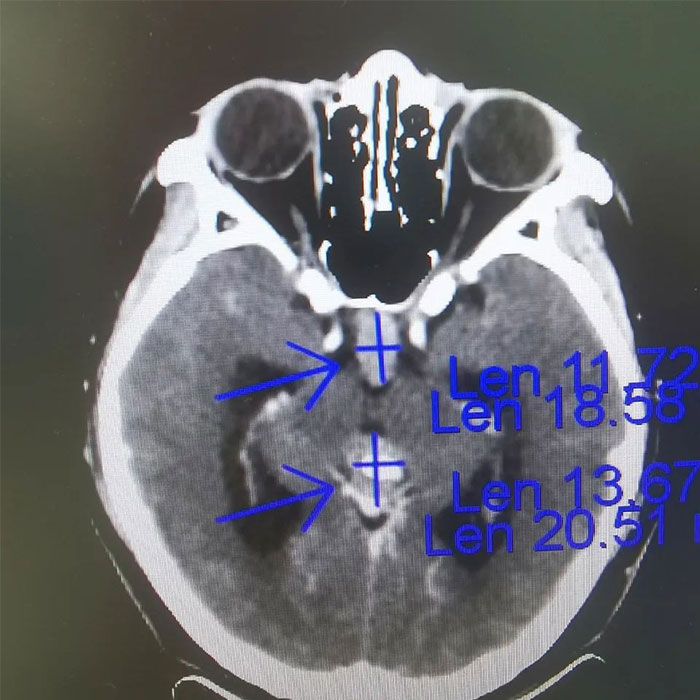

▲ 放疗前病灶影像定位

肿瘤科(放疗)王晓东主任详细了解了患者的病史,并进一步完善检查。在查体时,小刚表示近期感到头痛,偶有恶心呕吐。垂体增强MRI示:垂体术后,垂体区及松果体区占位,视交叉受压,右侧海绵窦局部受累,第三脑室扩大,梗阻性脑积水形成,提示病情进一步加重。